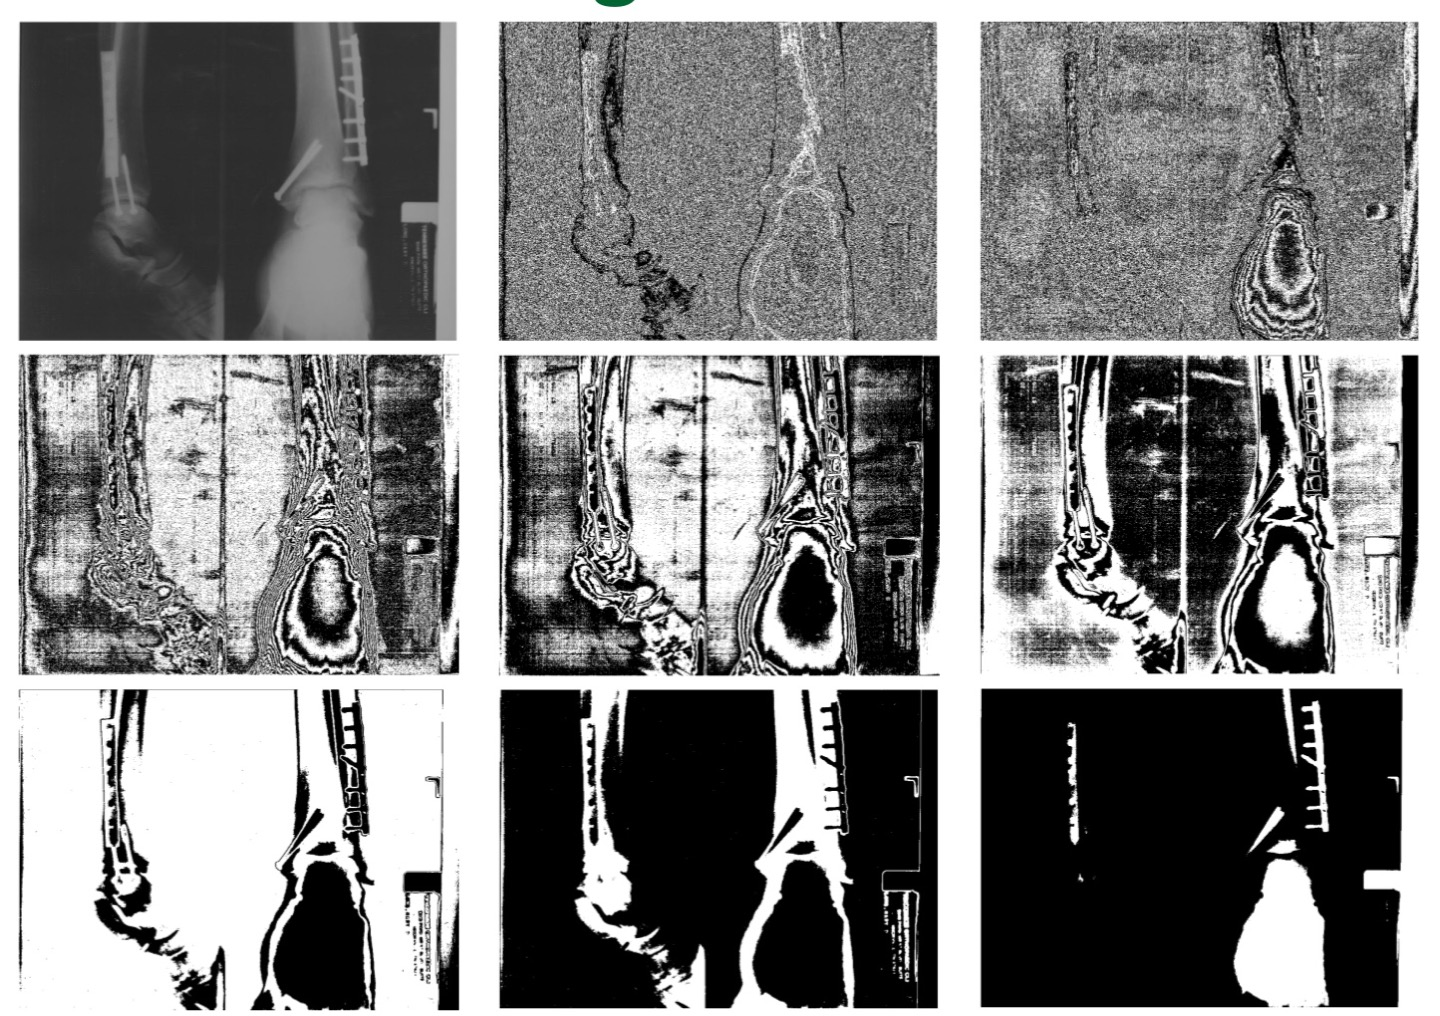

Constrast Stretching의 필요성은 아래 두 그림에서 알 수 있다. 우측 상단 원본 이미지에 대하여 Constrast Stretching 결과는 왼쪽 하단과 같고, Thresholding 결과는 오른쪽 하단과 같다. Thresholding은 특정 임계치를 넘게 되면 255 아니면 0으로 설정한다(flag에 따라 다름). 따라서 원본 이미지를 유지하기 보다는, 극단적인 대조 효과를 보인다. 하지만 Constrast Stretching 결과 대조효과를 더 극대화 하면서 원본 이미지를 유지함을 알 수 있다.

Bit-Plane Slicing

Bit-Plane Slicing은 이미지의 각 픽셀 값을 이진수로 표현했을 때의 각 비트 수준(Plane)을 분리하여 분석하거나 처리하는 영상 처리 방법이다.

이전에 Grayscale Pixel Value는 0~255의 범위를 가지는 8bits이다. 따라서 한 픽셀의 픽셀값은 8개의 2진수로 나타낼 수 있다. 따라서 전체 이미지에 대하여 각 픽셀을 비트 수준(Plane)에 대하여 0,1인지 구분하고, 1이라면 해당 Plane에 255를 나타내고 0이라면 0을 나타내는 방법이다.

$2^7$을 나타내는 비트 Plane을 보자. 255에 가까운 즉, 흰색에 가까울수록 해당 픽셀 값은 128을 넘길 것이다. 따라서 해당 비트 자리에는 1이다. 하지만 어두운 값은 해당 비트자리에는 0이 들어갈 것이다. 이처럼 극단적인 색상 비교를 하거나, 각 비트 수준으로 분리하여 처리할 때 이와 같은 방식을 사용한다.